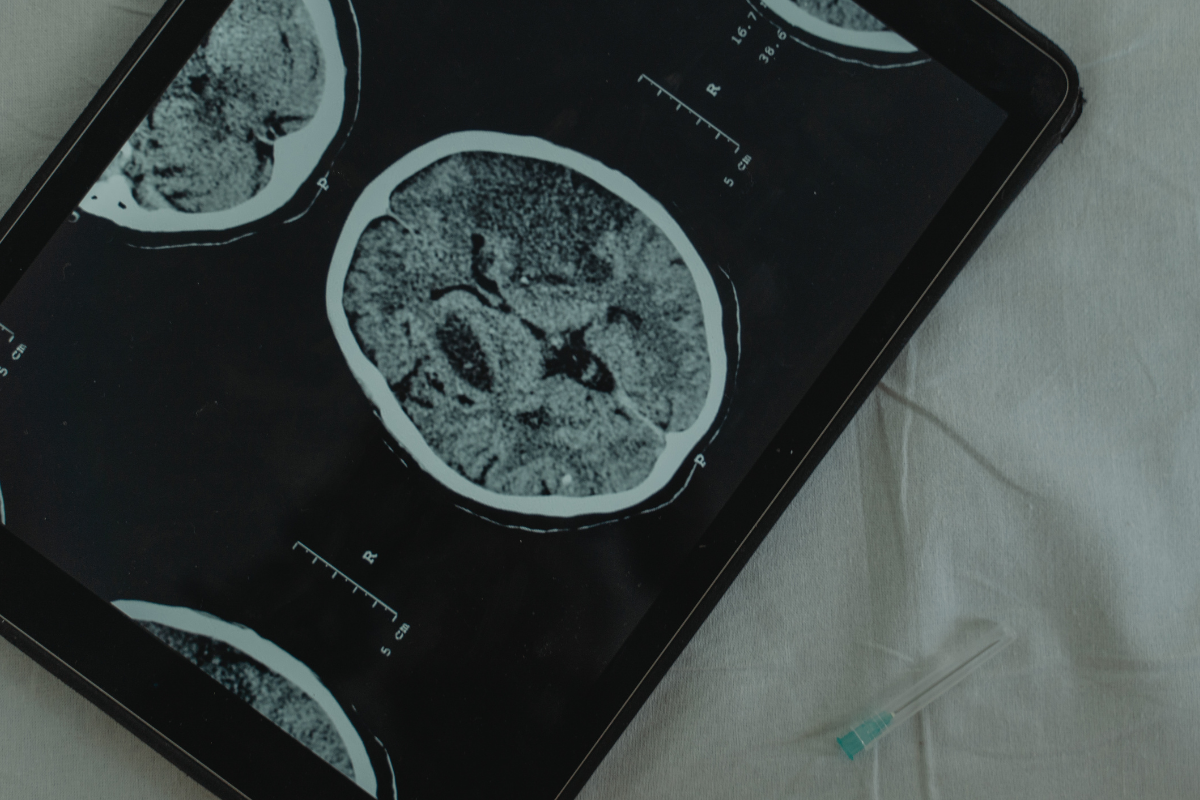

Как диагностируется опухоль головного мозга?

Если человек испытывает продолжительные головные боли, проблемы со зрением, судороги или неврологические изменения, врач может провести визуализационные исследования, чтобы подтвердить наличие опухоли.

Методы диагностики включают:

- МРТ (магнитно-резонансная томография): наиболее эффективный метод визуализации для обнаружения опухолей мозга.

- КТ (компьютерная томография): альтернатива МРТ для пациентов, которые не могут пройти МРТ-сканирование.